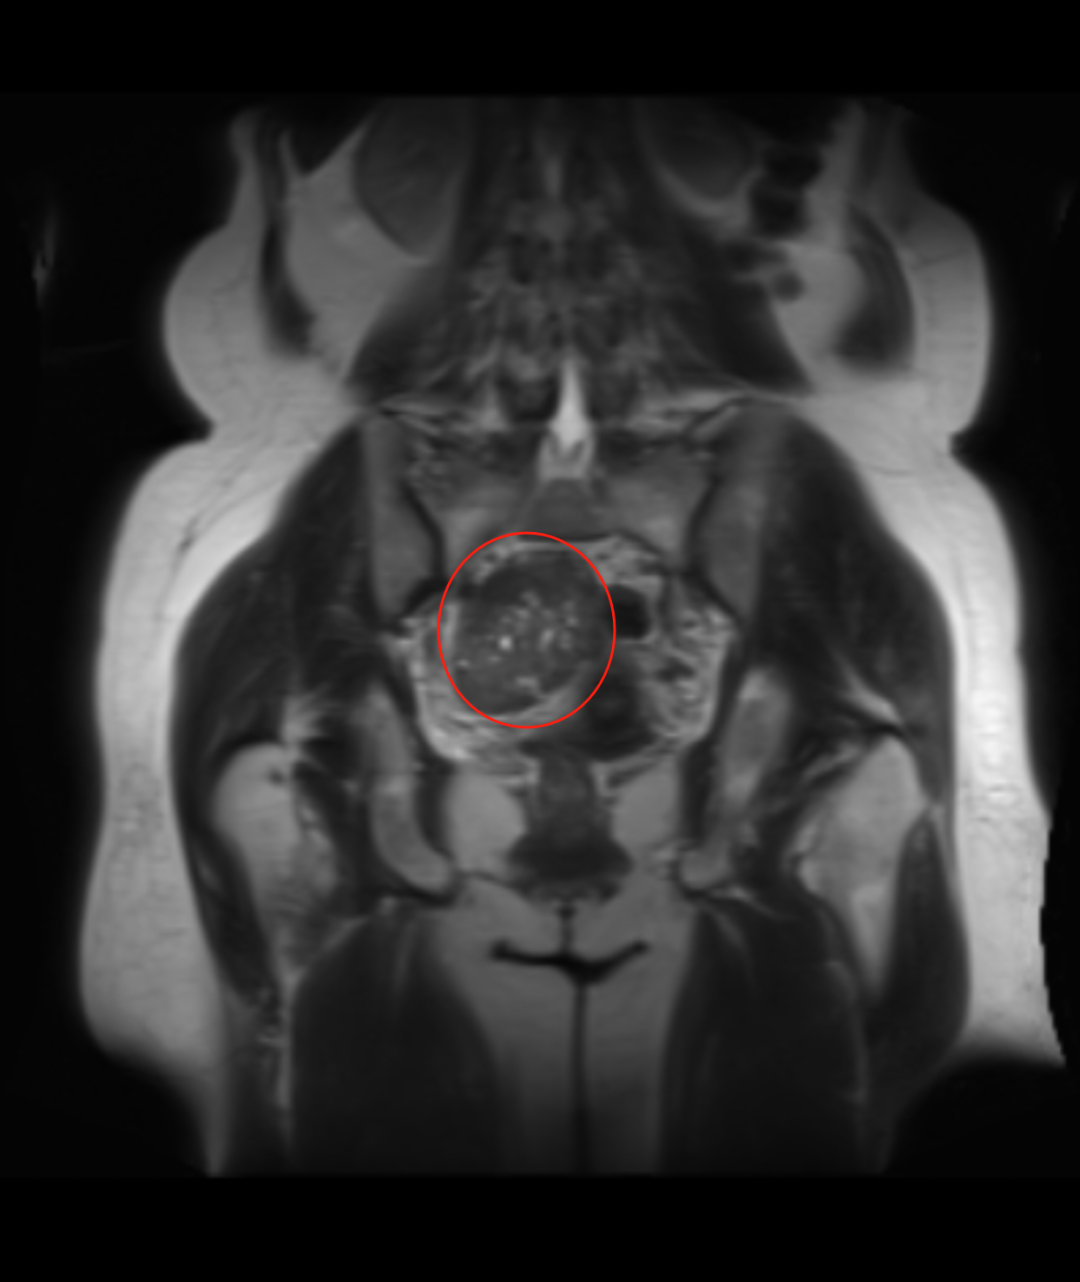

入院后,妇科团队为戴阿姨完善了盆腔增强 MRI、肿瘤标志物、性激素六项等相关检查。结合影像学特征和实验室结果,初步诊断为「子宫阔韧带良性肌瘤」。徐彩临院长带领妇科医护团队立即展开病例讨论:患者 53 岁,处于围绝经期,肌瘤体积较大(直径超 10 cm),虽考虑良性,但已可能压迫周围脏器,且存在潜在生长风险,符合手术指征。最终确定腹腔镜下右侧阔韧带肌瘤剔除术为首选方案,但手术难度大。